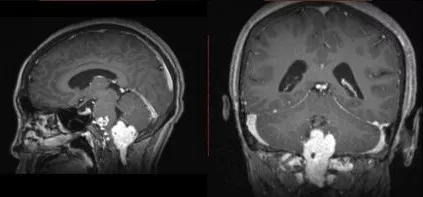

术前MR平扫提示颅颈交界区巨大占位,T1低密度,T2高密度,内有多量血管流空影。

增强MR提示病灶明显强化,伴瘤内血管影。除此以外,脑干侧方和腹侧可见扩张的静脉。